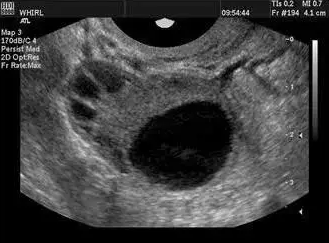

卵泡的正常生长受卵巢自身功能和下丘脑-垂体-卵巢轴以及中枢神经系统、内分泌系统的复杂影响。一般情况下,精子的寿命为2--3天,而排卵后卵子的寿命较短,15小时即会逐渐衰老;因此,排卵前两天至排卵后10小时是受孕的关键时间。当卵泡直径>10mm时,称优势卵泡;卵泡直径达>18mm时,称成熟卵泡。

一般认为成熟卵泡直径在18-25mm,妊娠机率较大,卵泡直径<18mm则不易妊娠。所以说卵泡发育不良,不能正常排卵或者排出的卵子质量不好,都会影响正常的受孕生育。